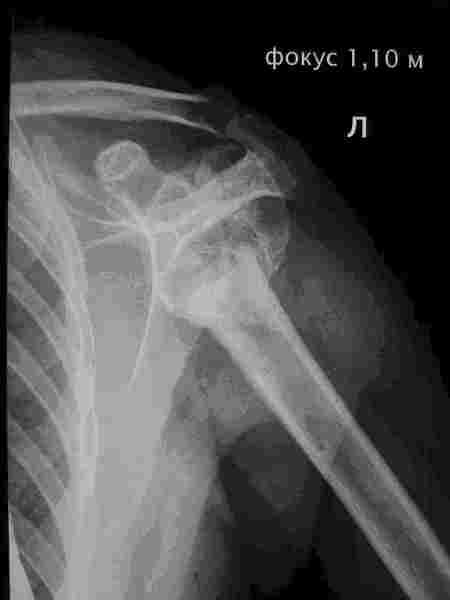

Вот молодая женщина 38 лет, обратилась с жалобами на ограничение активных движений в правом

плечевом суставе и незначительные боли. 2 года назад после ДТП получила раздробленный

перелом проксимального отдела левого плеча. Выполнялся накостный остеосинтез с

последующим удалением пластины через 7 мес. В настоящее время объем активных отведения и

сгибания в левом плечевом суставе в пределах 30-40 градусов, далее с лопаткой. На

рентгенограммах определяется ложный сустав хирургической шейки (фиброзное сращение). Ну